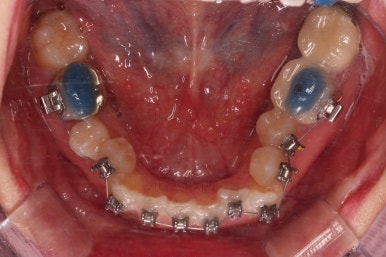

적절하게 디테일을 손보고 마무리를 합니다.

중간중간 보철된 치아도 있고, 위아래의 중앙선까지 100% 맞기는 힘든 상황이었지만 가급적이면 매우 잘 맞춰 드렸고요.

교합이라던지 가지런한 느낌도 좋네요.

우측만 위아래 뽑았지만 기능에는 문제 없이 교합을 마무리 했습니다.

부산치과교정 전후사진을 비교해 볼게요.

발치교정이라고 입매가 들어간 것도 아니고 오히려 더 예뻐졌죠?

중심선도 원하시는만큼 갖추었고, 가지런한 느낌도 좋고요.

21개월만에 전반적으로 매우 만족할만한 치료 결과를 얻었습니다.

이상 미니스크류와 비대칭적 발치를 통해 중심선(정중선, 중앙선)의 비대칭과 덧니를 개선한 부산치과교정 치료사례였습니다.